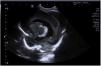

A male 24 was born at 246/7 weeks of gestation. Newborn weighed 540g and Apgar score 4/6/7. He was intubated in the delivery room due respiratory effort and during the first hours of life received endotracheal surfactant. Child remain stable without need of inotropic support and FiO2 of 25%. According to the unit protocol was monitored with a cerebral near-infrared spectroscopy (NIRS) and at 36h there was a sudden drop from values of 80 to 40. Diagnosis of shock was made and inotropic support and increase in ventilator settings. A cranial point of care ultrasound revealed a real time bilateral bleeding from the germinal matrix-intraventricular hemorrhage (videoclip 1 available online, Supplementary Fig. 1) with blood inside both lateral ventricles and the occipital horns (Figs. 1 and 2). Emergency transfusion was given and NIRS improved to 75 allowing to decrease inotropic support and respiratory support.